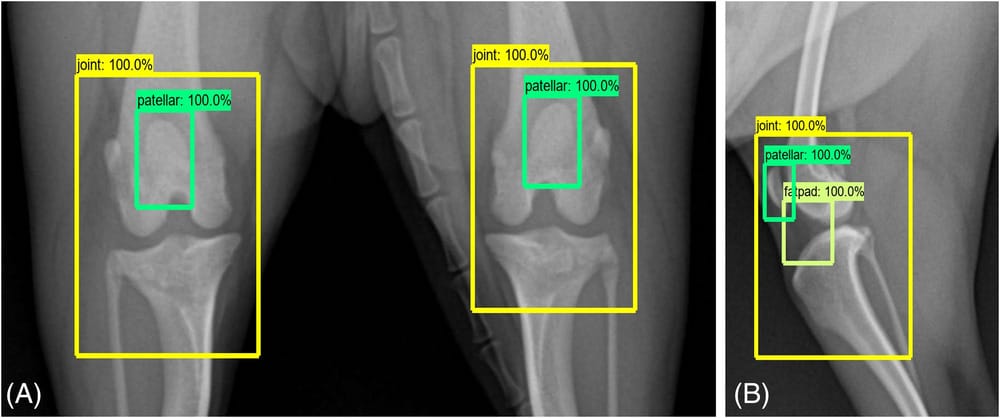

Detecting the components of the stifle joint using a Faster Region-based Convolutional Neural Network. A, Craniocaudal view. B, mediolateral view. The components of the stifle joint (i.e., stifle joint region, patella, infrapatellar fat pad region) are displayed through bounding boxes. The number on the upper left side of the bounding boxes indicates detection accuracy.